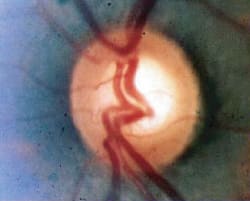

Fig. 2. Advanced glaucomatous cupping of the optic nerve with notching and loss of the

neuroretinal rim and extensive peripapillary atrophy. A corresponding superior arcuate field defect, threatening fixation, was seen on

standard automated perimetry. |

The large amount of RGC loss underlying detectable visual field defects in glaucoma means that our definition of early glaucoma should not be based solely on early visual field loss or high IOP. Only patients with preperimetric glaucoma -- identifiable optic disc abnormalities but no field loss -- should be considered to have early or mild glaucoma (See Figure 1). Once a visual field defect is detectable, the patient can be said to have moderate to severe glaucoma, depending on the degree of field loss (See Figure 2).